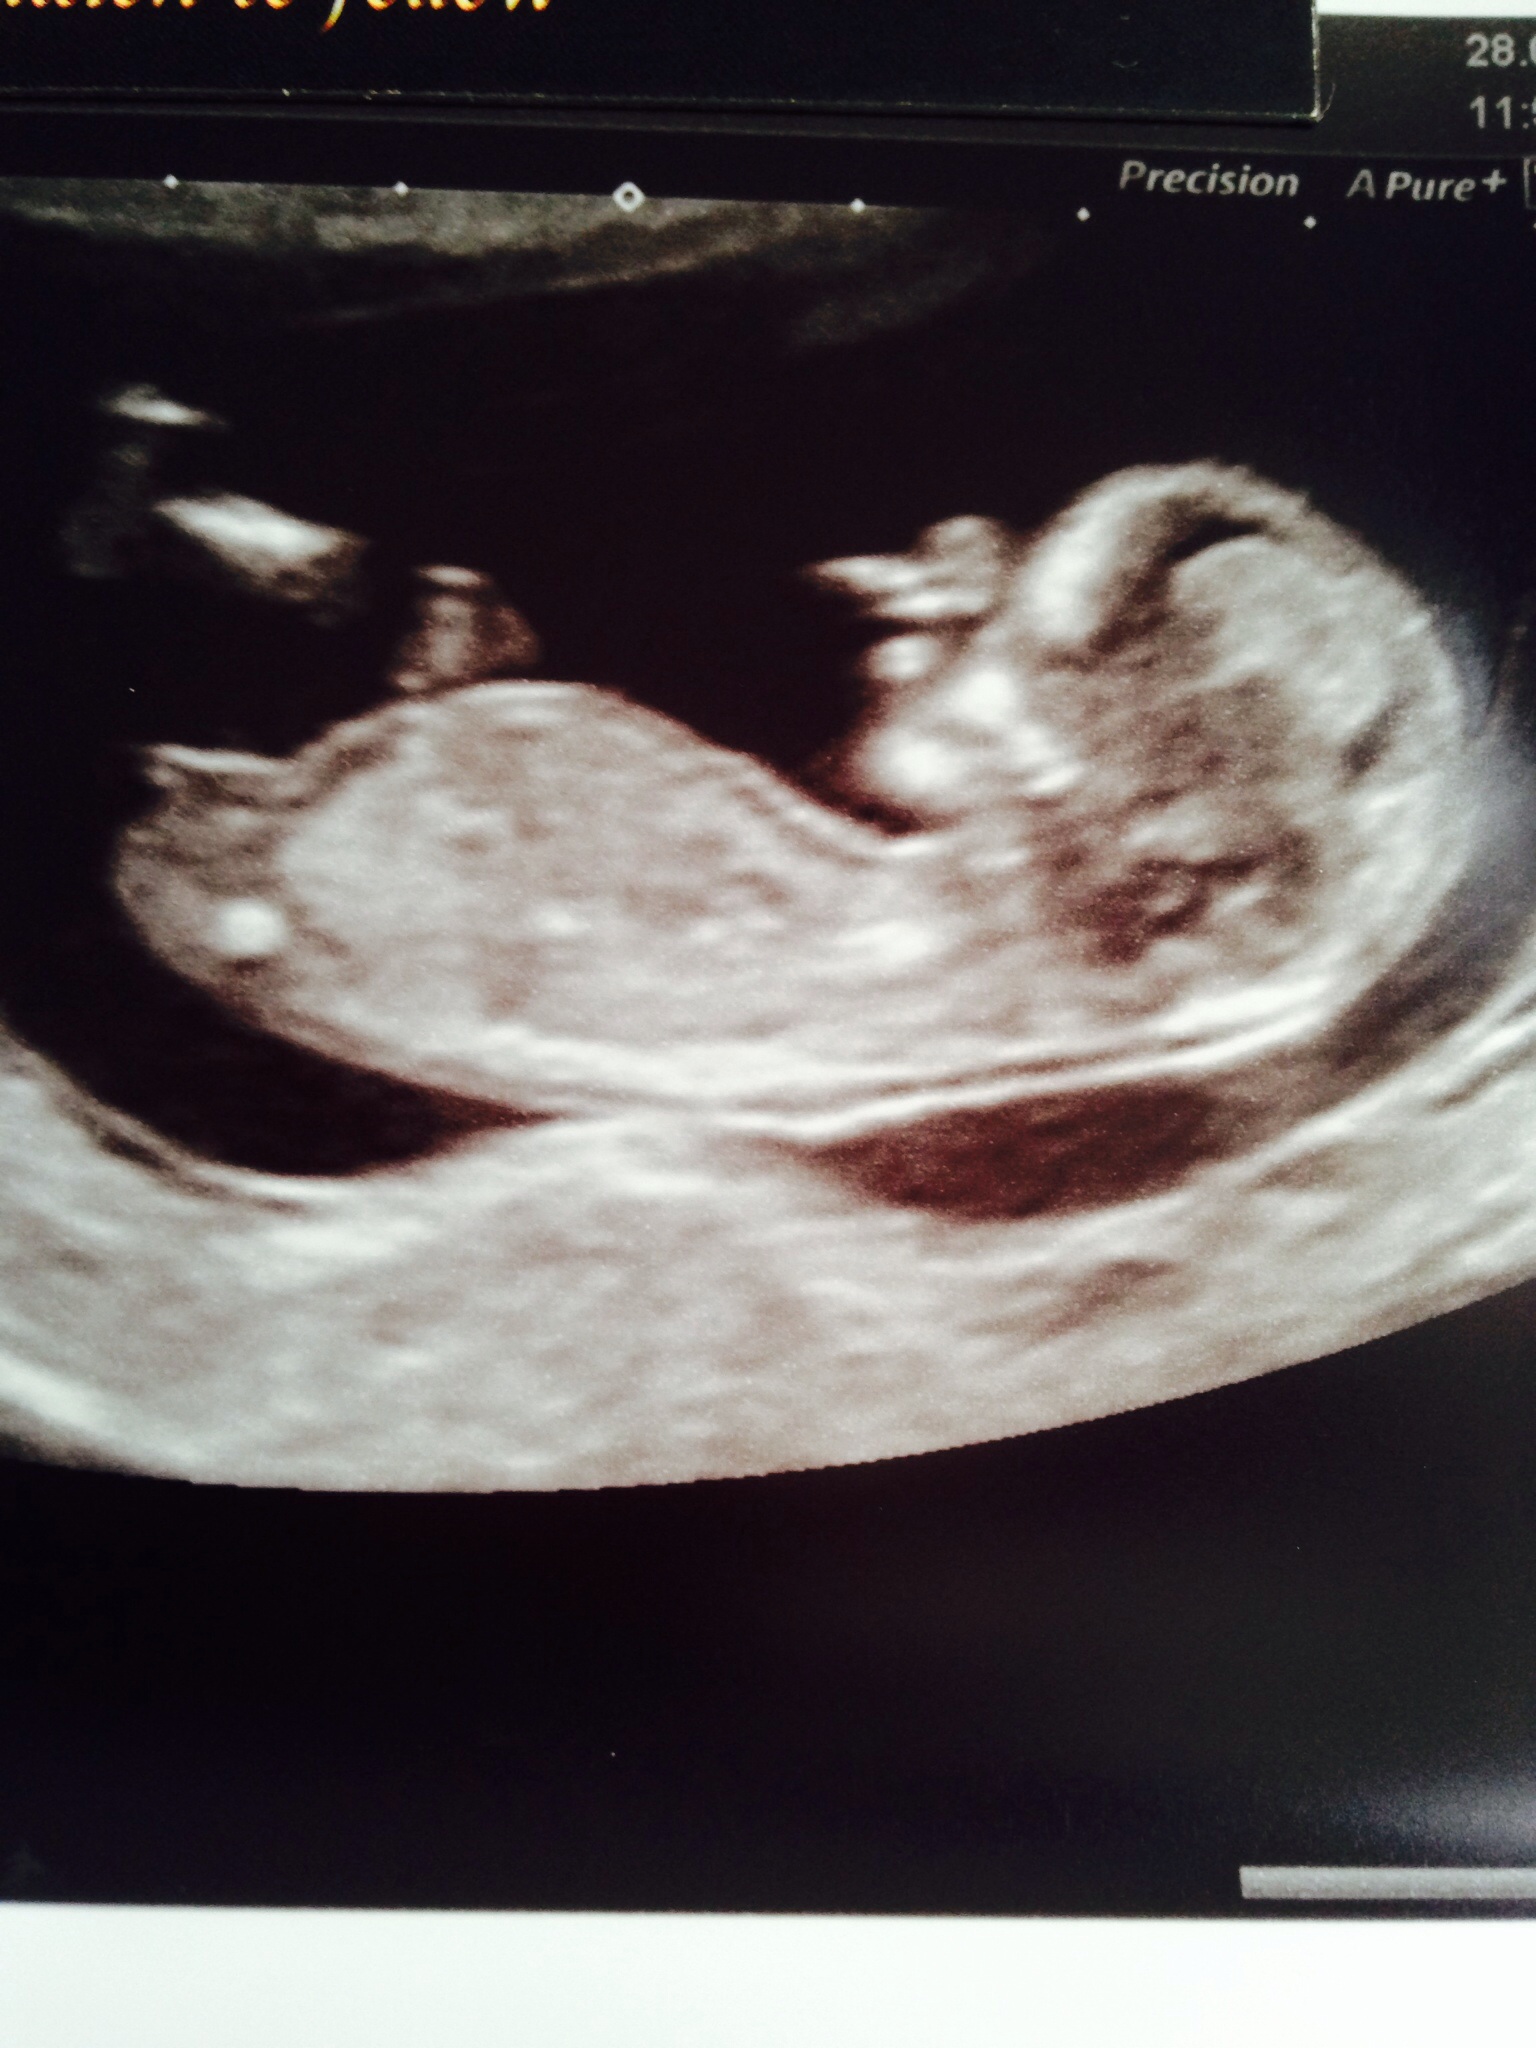

Girl!

Maybe girl xx

Girl but still early so may rise... But I think it prob won't;)

I actually think boy, it looks short and on the rise with a slightly bulbous end. But I think it could go either way still..